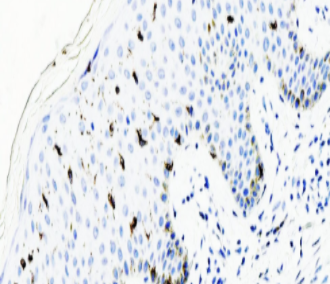

Langerin抗体 是一种特异性识别朗格汉斯细胞(Langerhans cells,LCs)表面II型跨膜受体(C型凝集素)的免疫检测工具。该受体定位于LCs特有的Birbeck颗粒(由层状压缩膜构成的胞质细胞器),通过甘露糖结合特性介导抗原内吞和非经典抗原提呈途径,在表皮和黏膜的免疫应答启动中发挥核心作用。该抗体在脾脏、淋巴结、胸腺、肝脏、肺和心脏组织中均有表达,其核心诊断价值在于:①特异性标记LCs来源的朗格汉斯细胞组织细胞增生症(LCH);②有效区分LCH与其他非朗格汉斯细胞的组织细胞增殖性疾病,为组织细胞疾病的病理分类提供关键分子依据。

阳性部位:

细胞质/膜